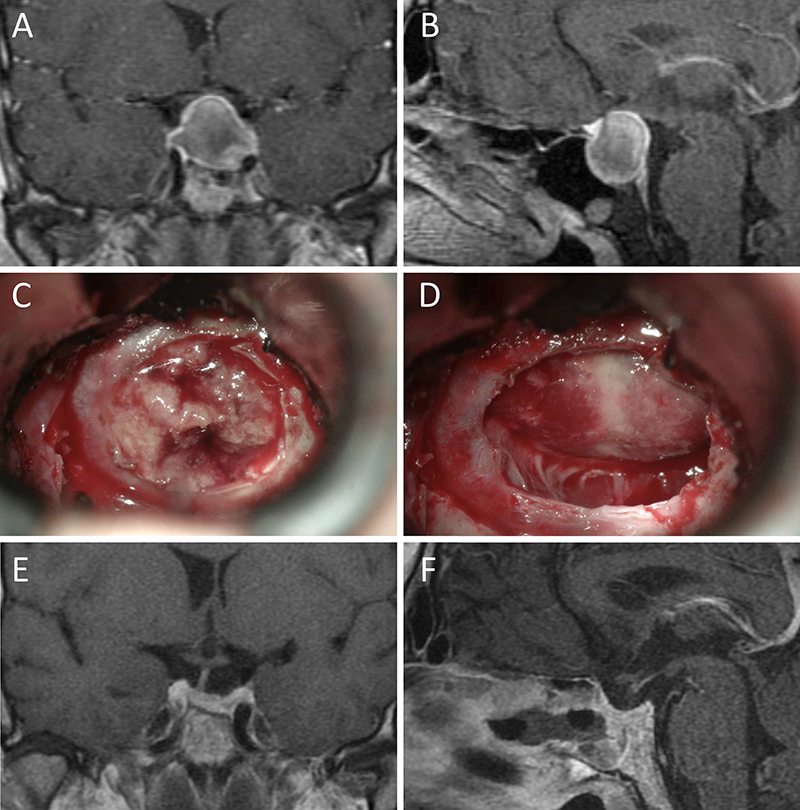

Figura 3: Macroadenoma no funcionante en un hombre de 64 años. El paciente presentó en el preoperatorio déficit visual que mejoró tras la cirugía. A-B: RM preoperatoria; C-D: intraoperatorio; E-F: RM postoperatoria.

Figura 4: Macroadenoma no funcionante en mujer de 32 años. La paciente presentó en el preoperatorio déficit visual que mejoró tras la cirugía. A-B: RM preoperatoria; C-D: intraoperatorio; E-F: RM postoperatoria.